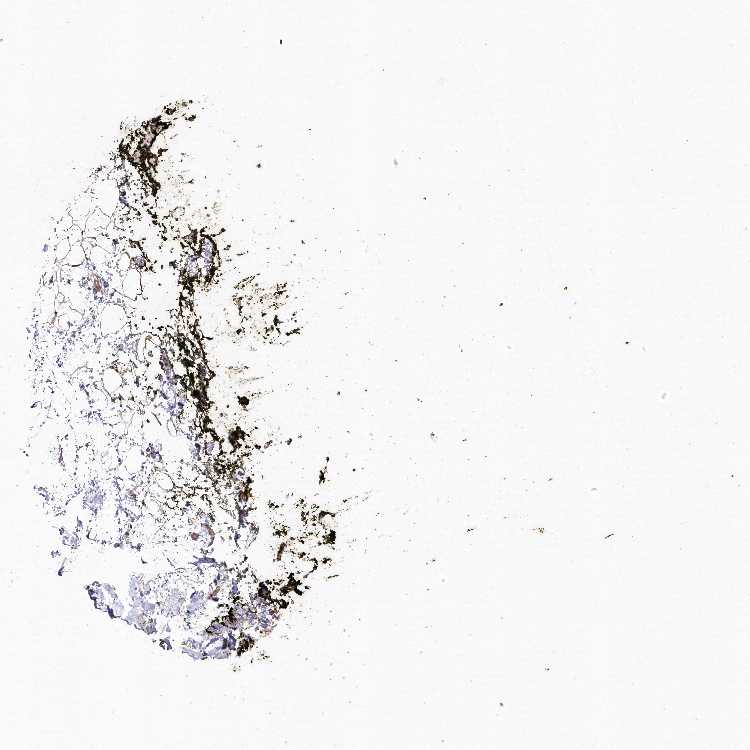

SOFT TISSUE 1 - Antibody stainingi

Antibody staining in the annotated cell types in the current human tissue is reported as not detected, low, medium, or high, based on conventional immunohistochemistry profiling in selected tissues. This score is based on the combination of the staining intensity and fraction of stained cells.

Each image is clickable and will lead to virtual microscopy that enables deeper exploration of all samples and also displays staining intensity scores, fraction scores and subcellular localization as well as patient and tissue information for each sample.

Antibody HPA037770Antibody HPA037771

Fibroblasts Not detectedLow

Peripheral nerve -Low